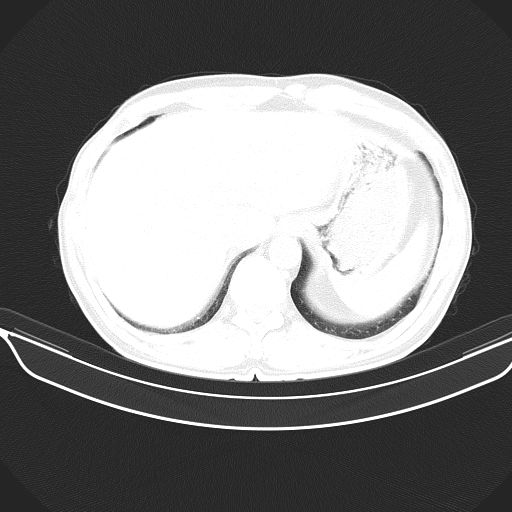

以下是引用shuiyuan在2010-3-1 10:45:00的发言:[br]考虑左肺上叶中心型肺癌伴阻塞型炎症,邻近胸膜受侵。

以下是引用心路寻觅在2010-3-1 10:23:00的发言:[br]1、考虑左肺上叶周围型肺癌[br]2、右上肺陈旧性病灶。[br][br][本贴已被 心路寻觅 于 2010-3-1 10:40:18 修改过]